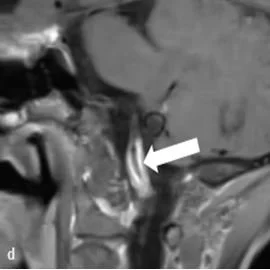

Vessel Wall Magnetic Resonance Imaging of a Nonstenotic Craniocervical Vertebral Artery Dissection (Sept 2022)

We report how VWI can facilitate diagnosis of a craniocervical vertebral artery dissection.